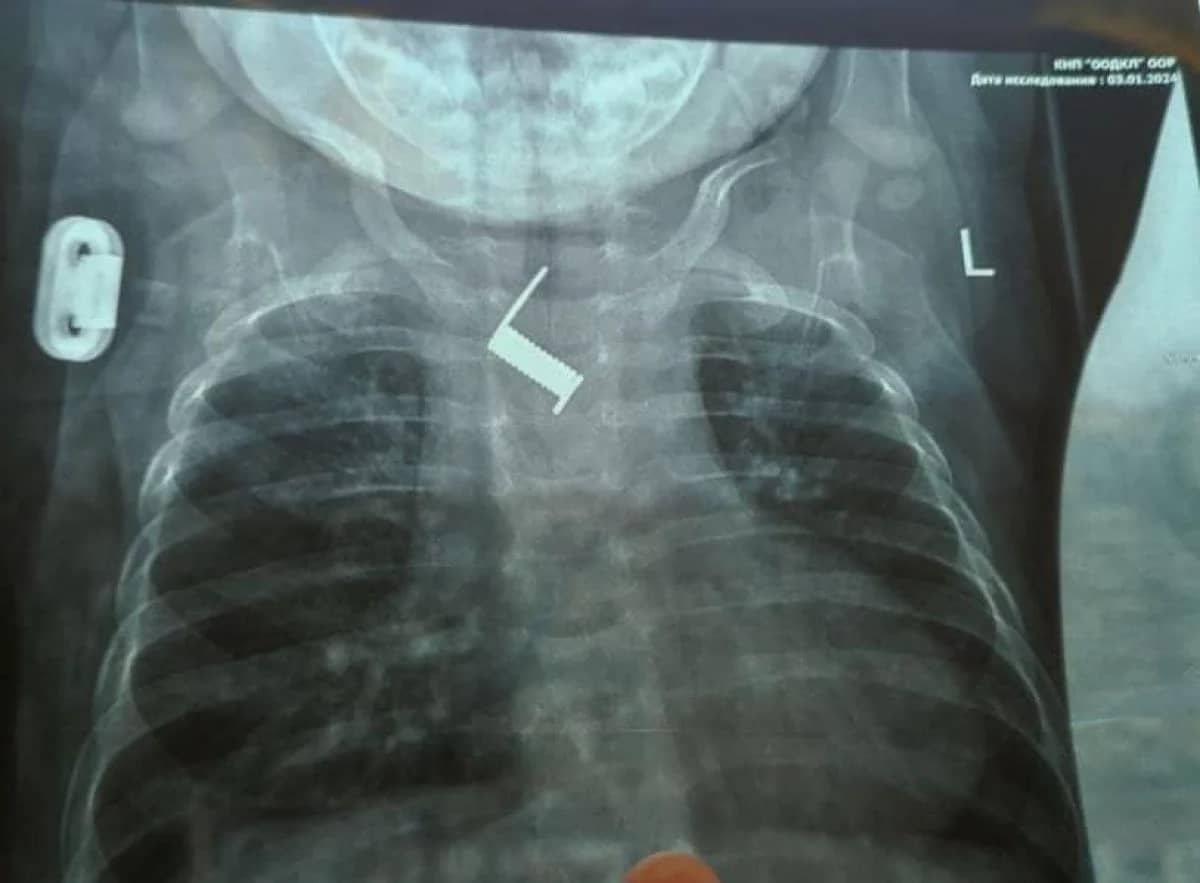

В Одесі врятували малюка з пружиною у стравоході: до того крихітку два тижні "лікували" від бронхіту